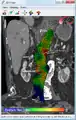

An aneurysm ruptures if the mechanical stress (tension per area) exceeds the local wall strength; consequently, peak wall stress (PWS),[30] mean wall stress (MWS),[31] and peak wall rupture risk (PWRR)[32] have been found to be more reliable parameters than diameter to assess AAA rupture risk. Medical software allows computing these rupture risk indices from standard clinical CT data and provides a patient-specific AAA rupture risk diagnosis.[33][34][35] This type of biomechanical approach has been shown to accurately predict the location of AAA rupture.[34][35][36]